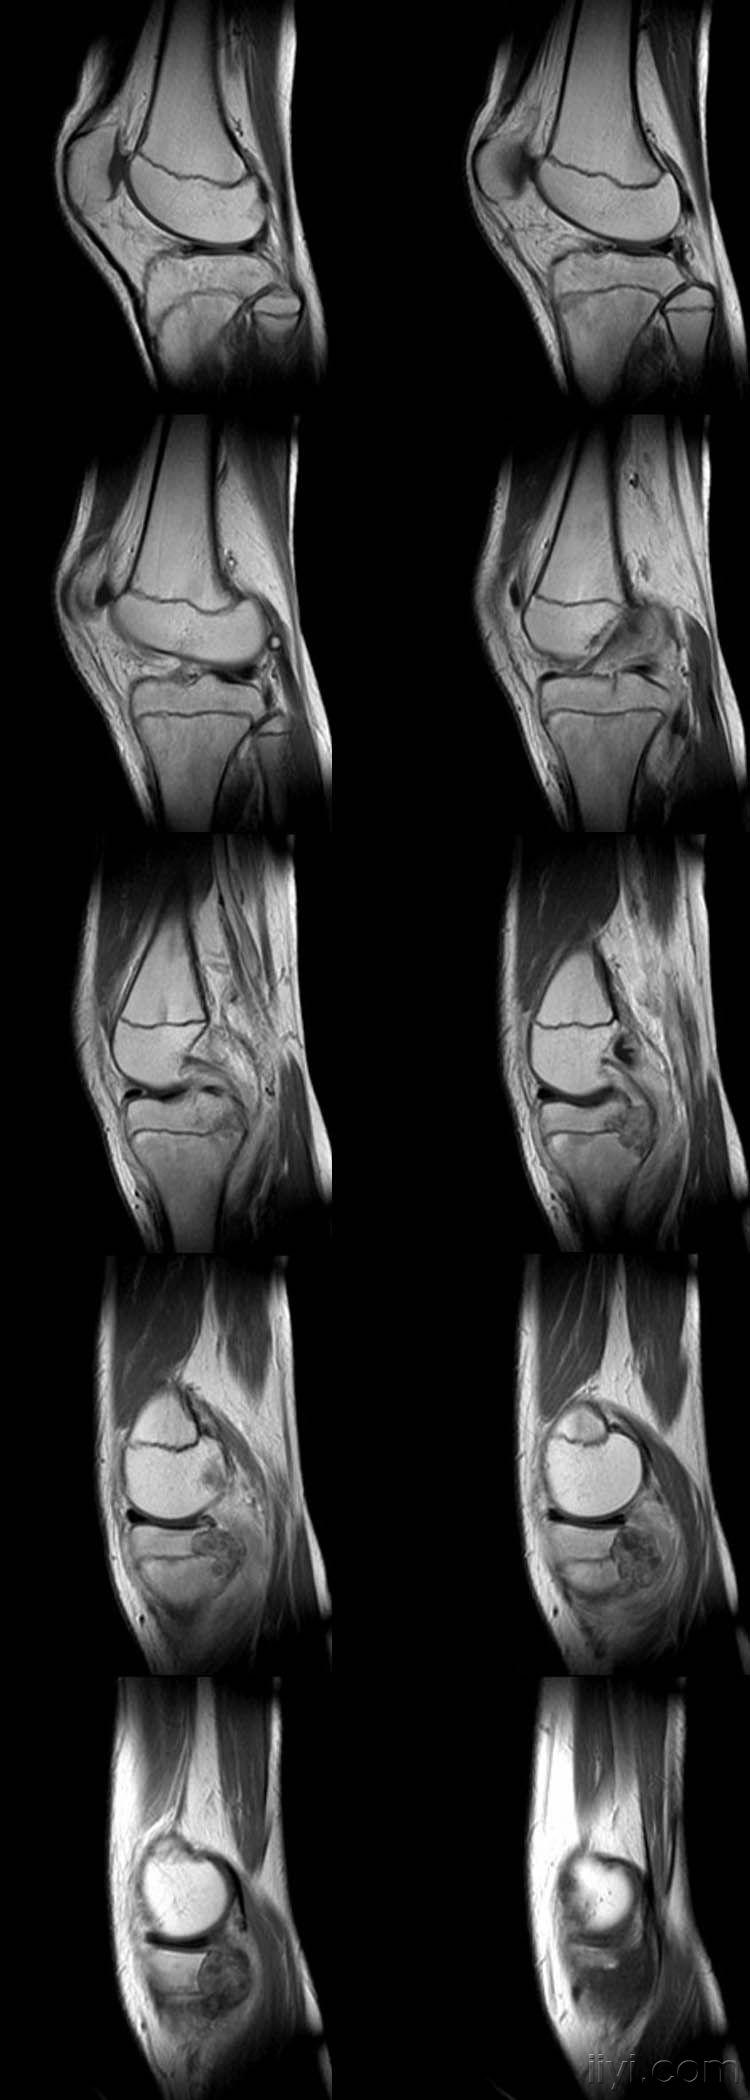

女,14岁,膝关节外伤后疼痛4月余。

向老师学习,恶性肿瘤可能,骨肉瘤?